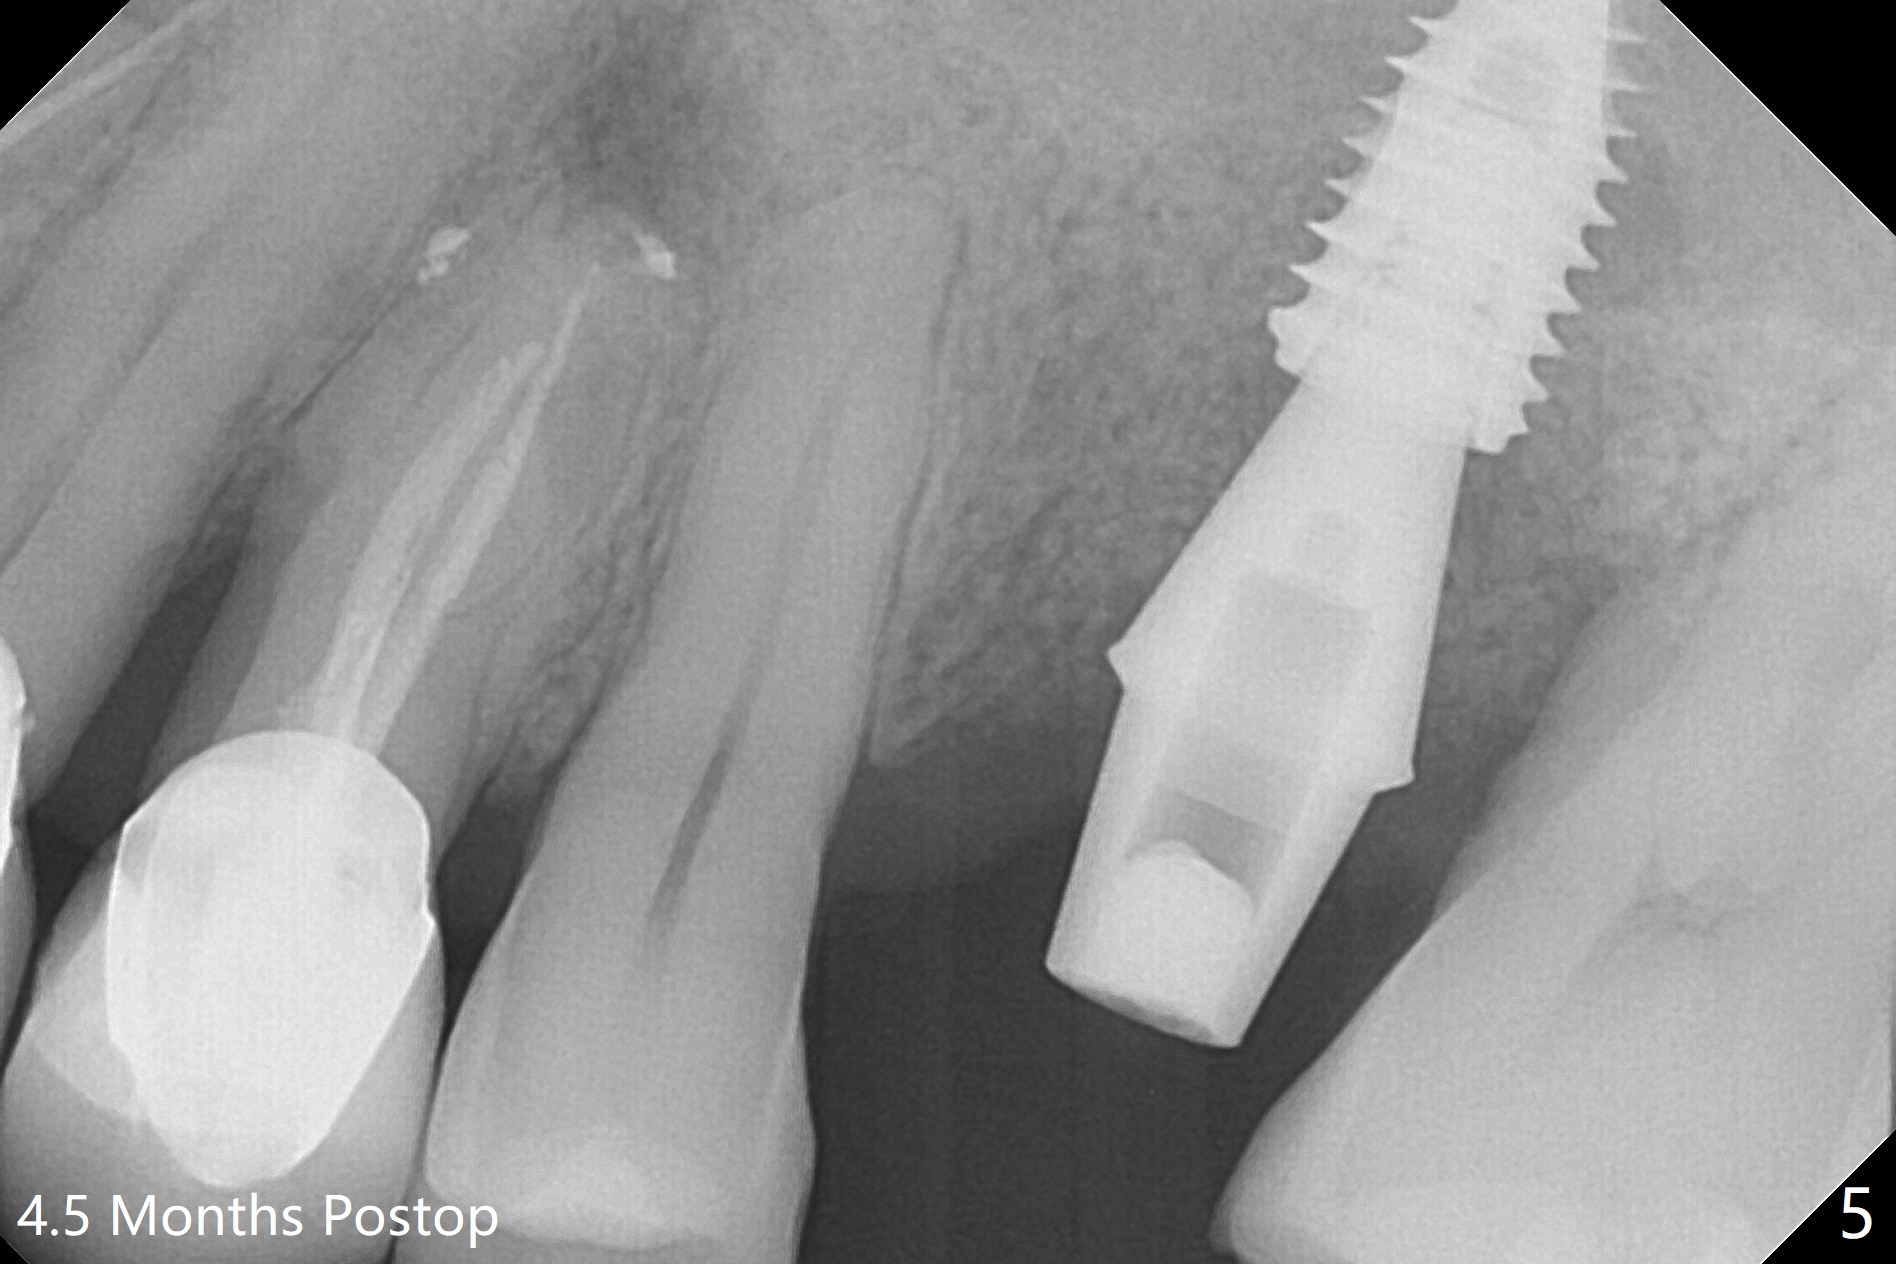

Six months post 2nd placement at #14, the 5x11 mm IBS implant is unstable. The patient smokes a cigarette a day.  After implant removal, the palatal wall of the osteotomy is intact, although low.  With removal of minimal granulation tissue, a 5x10 mm IS dummy implant is placed with stability and slightly subgingival palatal (Fig.1,2).  A 5x8.5 mm definitive implant is placed with ~ 40 Ncm and 3-4 mm subgingival palatal (Fig.3,4).  A 5.7x5.5(5) mm abutment is placed to hold periodontal dressing in place.  If the implant fails again, bone graft should be placed.  The abutment and implant are stable 4.5 months postop (Fig.5); a provisional is fabricated for progressive loading.  The provisional at #14 is narrow mesiodistally, while the tooth #15 is mesially tilted and shifted because of chronic periodontitis and 1 year 4 months of edentulism (Fig.6*).  Limited orthodontics is necessary prior to final restoration.  The 1st step is to raise the occlusion with #14 temporary reline (Fig.7 *); the tooth #15 is distalized initially with a separator, which is inefficient.  It appears that brackets and bands should be placed for distalization.  A month post banding, open coil spring is placed between #14 and 15; with occlusal composite on the opposing tooth (#19) (Fig.8), the tooth #15 is distalized instantly probably related to its periodontal condition (Fig.9 mirror view).  The tooth #15 is further distalized 2 weeks post open coil spring placement (Fig.10).  To act an anchorage, the abutment needs to be torqued with wrench (25-30 Ncm) and the provisional has to be permanently cemented.  The distalization appears to be ~ 1 mm shy 1.5 months post open coil (Fig.11).